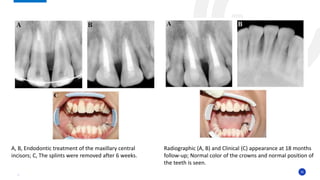

Radiographic (A, B) and Clinical (C) appearance at 18 months

follow-up; Normal color of the crowns and normal position of

the teeth is seen.

A, B, Endodontic treatment of the maxillary central

incisors; C, The splints were removed after 6 weeks.